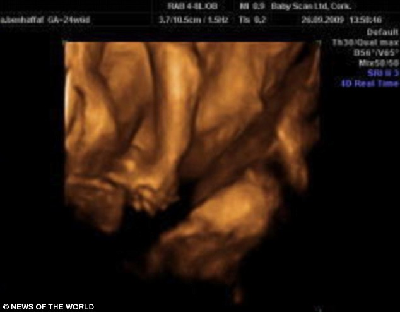

這是連體嬰兒母親懷孕24周的掃描照片,圖中可見胎中嬰兒手牽著手。

據(jù)介紹,兩個小家伙于去年12月出生在倫敦大學(xué)醫(yī)院。早在安琪懷孕12周的時候,B超顯示,她懷上一對連體嬰兒。在24周的時候,則能從B超照片中看出,兩個小家伙的手緊緊握在一起,親密無間的樣子,讓人看了不免動容。